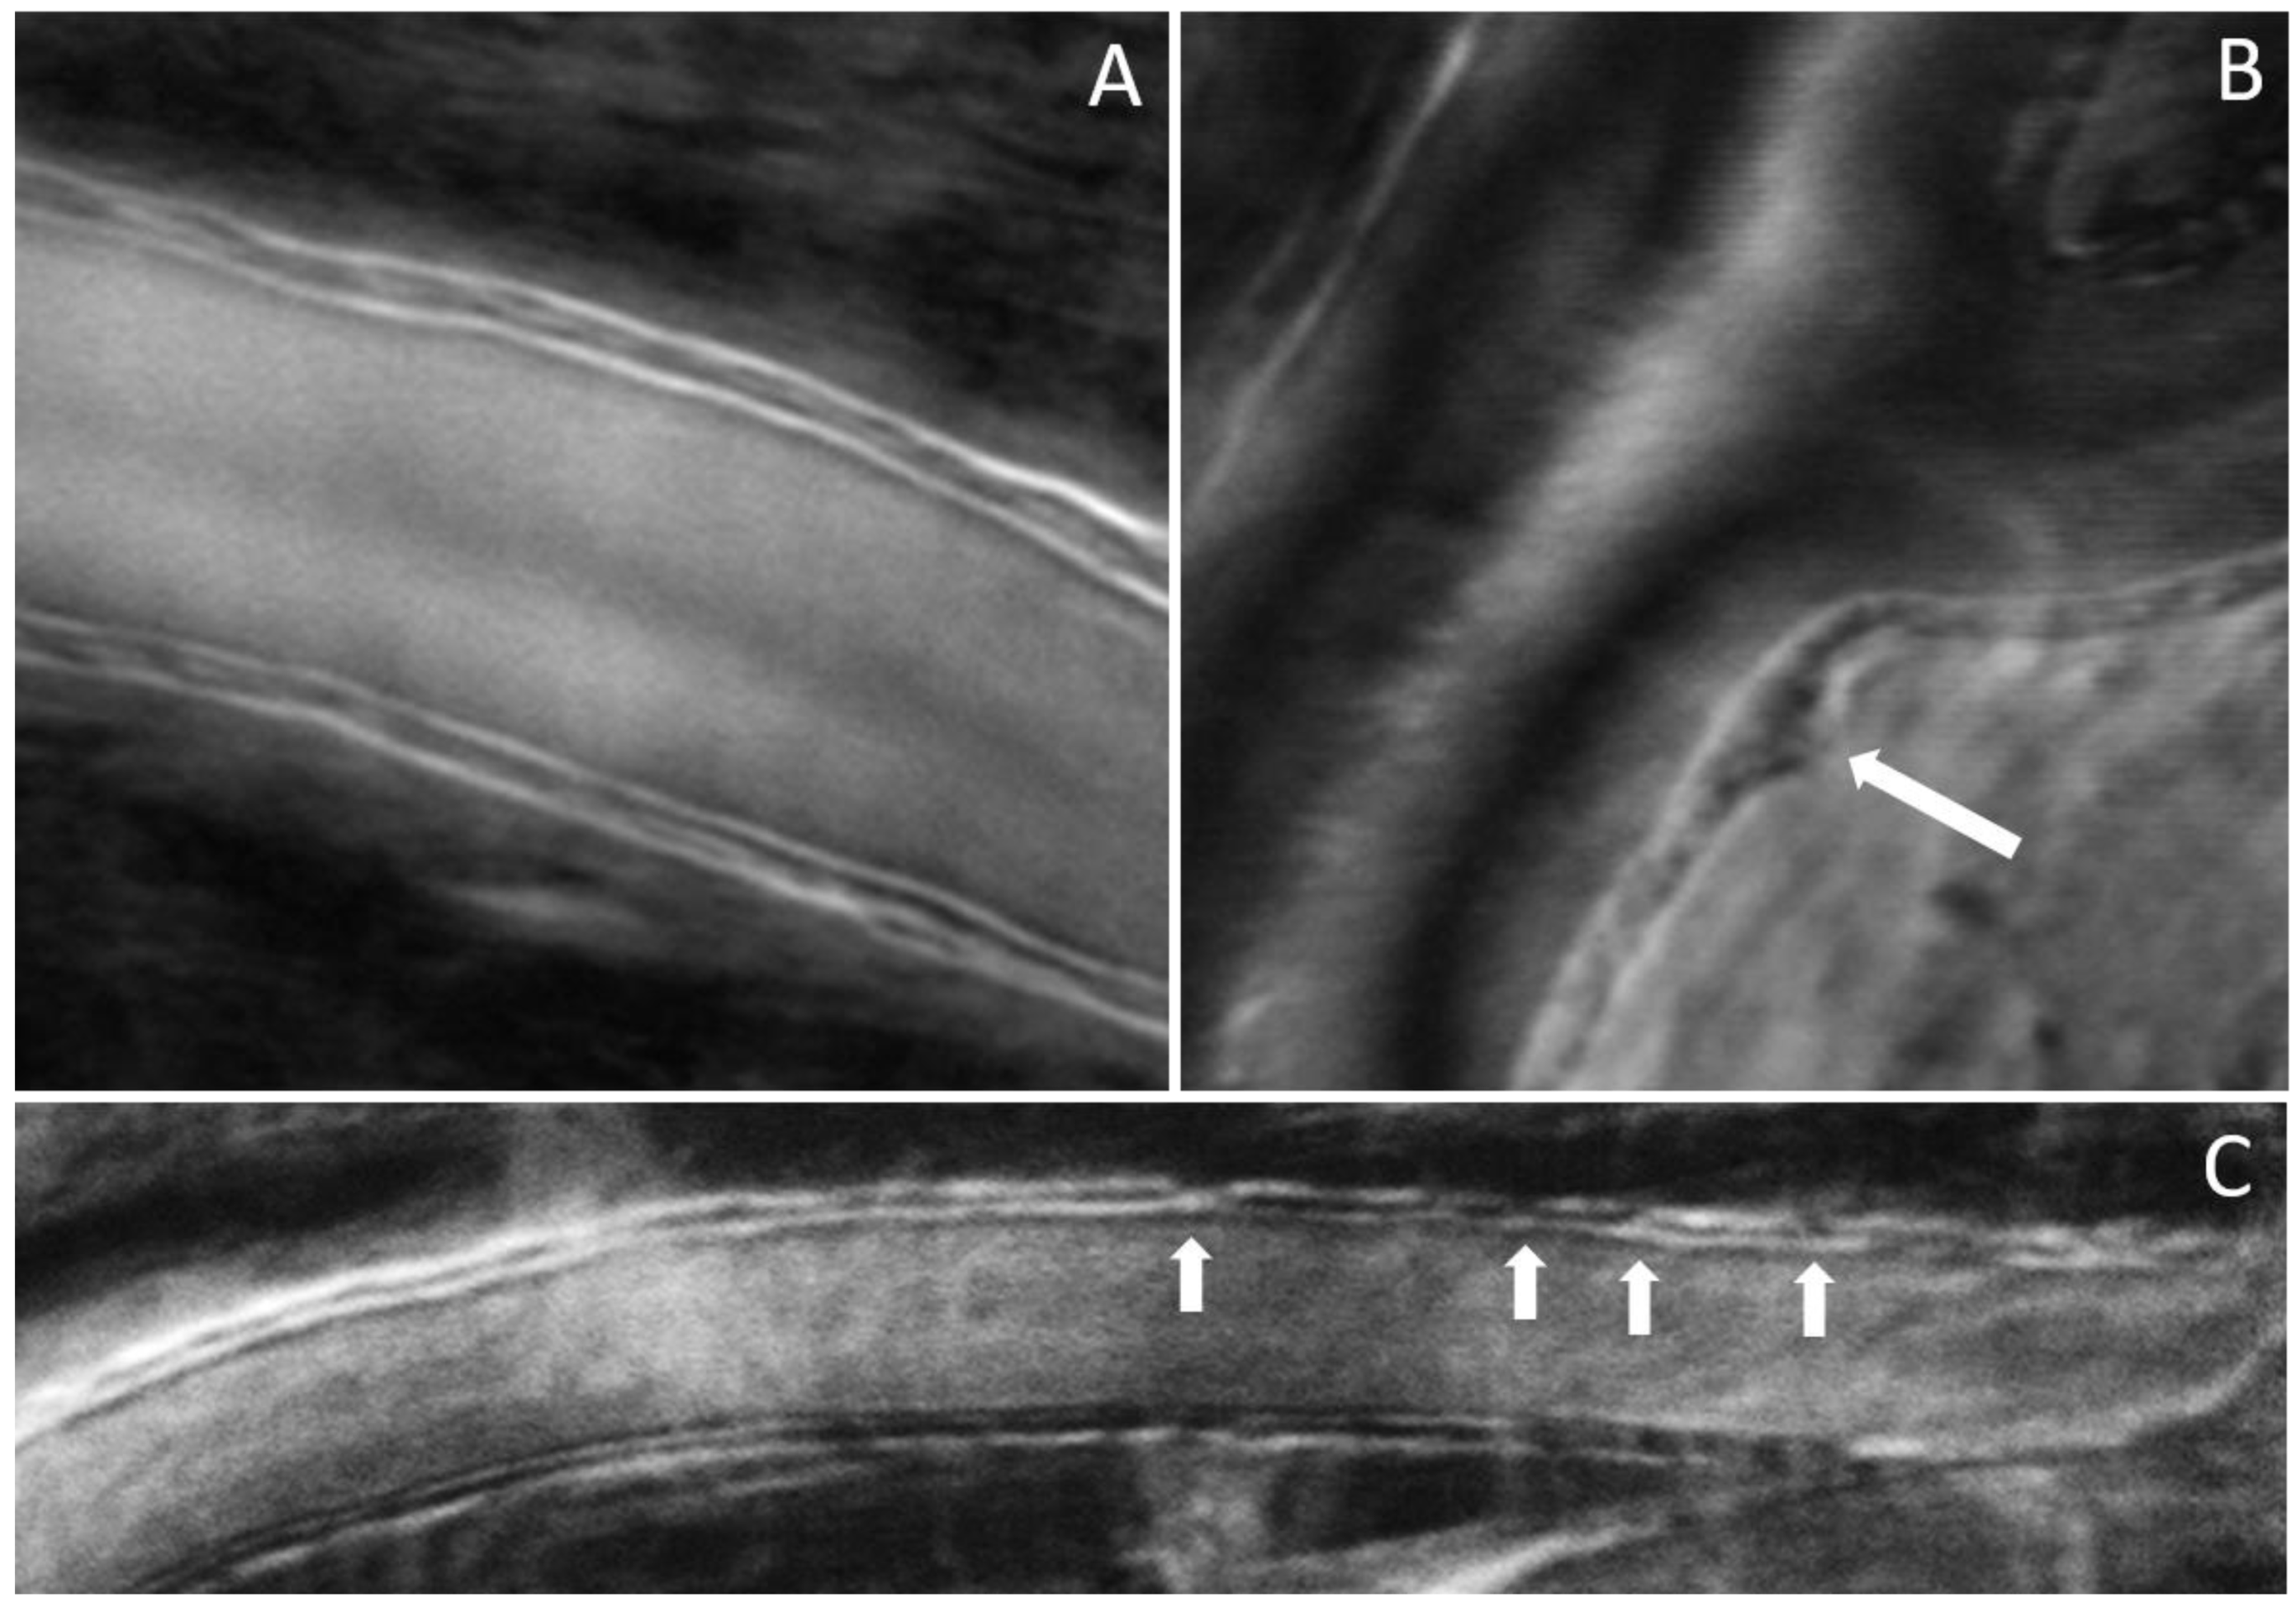

The results shown in Figure 4, Figure 5 and Figure 6 were obtained from a healthy subject. Figure 7, Figure 8 and Figure 9 show images obtained from eyes with different levels of DR severity. Figure 7A is from the same control as in Figure 4, Figure 5 and Figure 6. Figure 7B,C are from two subjects with T1D but no DR. Figure 8A,B correspond to subjects with mild nonproliferative DR (NPDR), C is from a moderate NPDR subject, D is from a severe NPDR subject, and E/F is from a proliferative DR (PDR) subject. All images in Figure 7 and Figure 8 are MPG except for Figure 8F, which is the STD image corresponding to Figure 8E. Similarly to Figure 6, Figure 9A shows the vessel diameter (VD—magenta) and lumen diameter (LD—green) as a function of position along the vessel for a scan partially shown in Figure 8C, and Figure 9B displays the WLR.

Figure 7.

(A) Control; (B,C) no DR; arrows indicate disruption of the wall integrity.

Figure 8.

(A,B) Mild NPDR; (C) moderate NPDR; (D) severe NPDR; (E,F) PDR; arrows in (A,B) indicate disruption of the wall integrity; arrow in (D) indicates a microaneurysm.

The imaging method and the analysis procedure presented here enable the identification of structural abnormalities that are the result of disease, DR due to T1D in particular in this study. Loss of structural integrity of the blood vessel wall may result in MAs, a hallmark lesion of DR, which may leak or rupture and further cause visual decline. Figure 7 and Figure 8 show several examples of structural distortions in subjects with various levels of DR severity. The healthy eye illustrated in Figure 7A has strong continuous vessel borders. In contrast, the rest of the images in Figure 7 and Figure 8 show disruptions in the vessel walls, indicated by the arrows, either bulging or local thinning of walls that may become the location of future MAs like the one shown in Figure 8D (arrow). Additional videos (Videos S2 and S3) and an image (Figure S1) are included in the Supplementary Materials to illustrate very faint blood flow through the MA, which is confirmed in the STD image by the very dim motion contrast bulge next to the blood vessel. Figure 8E,F show significant variations in the lumen diameter in a portion of the vessel that has no additional branches (white oval) for a PDR subject. It is expected that the lumen diameter changes across a branch for flow conservation while it should be relatively constant in between branches. DR might affect the elasticity/stiffness of the vessel wall, and distortions could occur, such as those illustrated here. Similarly, Figure 9 shows tremendous variations in the lumen and vessel diameters along a vessel of an eye with moderate NPDR. It seems that the wall thickness is relatively constant while the lumen/vessel diameter varies significantly (also arrows in Figure 8C). The result is a large variation in WLR along the vessel, as shown in Figure 9B, in between branches. Future prospective studies may elucidate whether increased variation in WLR is associated with future problems related to vessel wall integrity.